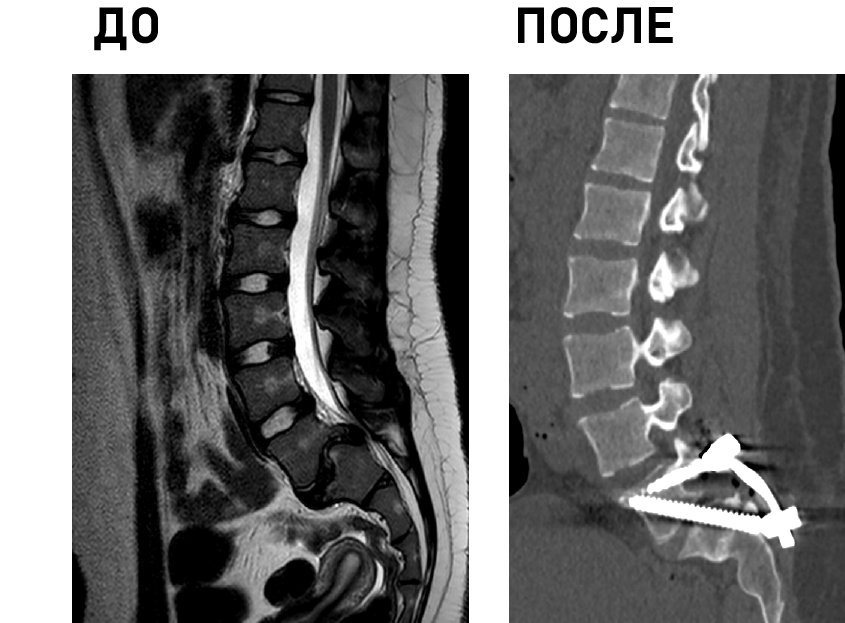

Технические возможности: технологии малоинвазивной (MIS) и реконструктивной хирургии, костнопластические материалы и инструментальная фиксация, современное силовое и ультразвуковое операционное оборудование, навигация, нейромониторинг.